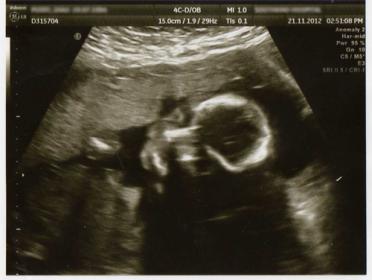

12 week scan today and had no idea about nubs or skull shape prediction until today.

The scan guy said that looking at nub, he thinks it could be a girl but early days yet. Maybe the nub is not showing in pictures and someone could have a guess on skull shape as bottom picture is quite clear.

What do you think?